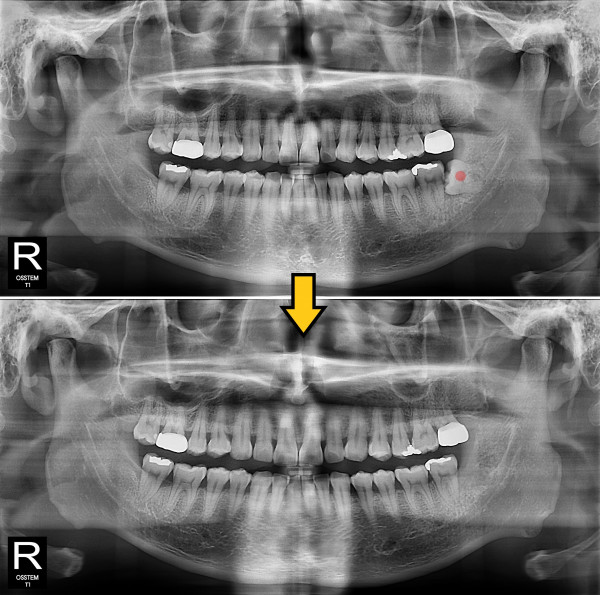

사랑니발치 완전 매복 사랑니

826e40416d712e6cd444a78bde93df4b_1767858140_0429.jpg